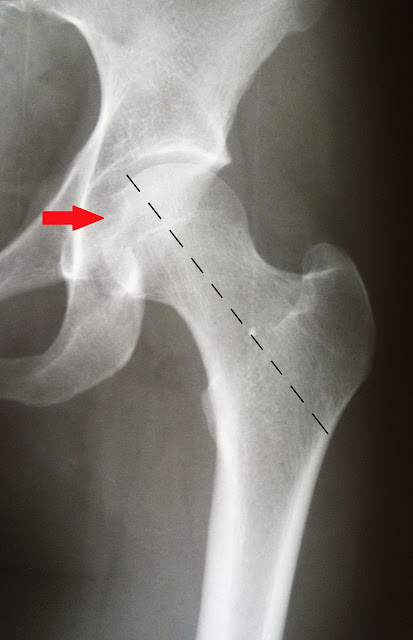

Для уменьшения вероятности истирания связки головки бедренной кости, ligamentum capitis femoris, важно, чтобы ее продольная ось имела отклонение во фронтальной плоскости и максимально возможную глубину ямки вертлужной впадины, fossa acetabuli. При натяжении связки головки бедренной кости, ligamentum capitis femoris, за счет приведения бедра, os femur, и наклона таза, pelvis, вниз в медиальную сторону, рационально расположение ямки головки бедренной кости, fovea capitis femoris, а значит, дистального конца связки головки бедренной кости, ligamentum capitis femoris, в середине либо в нижнем секторе медиальной поверхности головки бедренной кости, caput femoris. Подобное расположение ямки головки бедренной кости, fovea capitis femoris, прослеживается на рентгенограммах неизмененного тазобедренного сустава, articulatio coxae (Рис. 14).